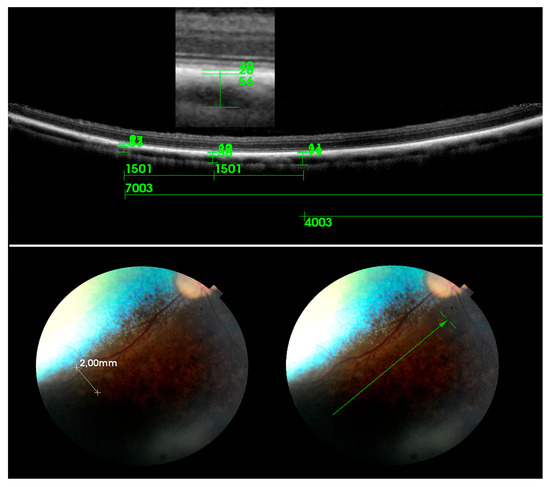

2.2. OCT Scan and Data Analysis